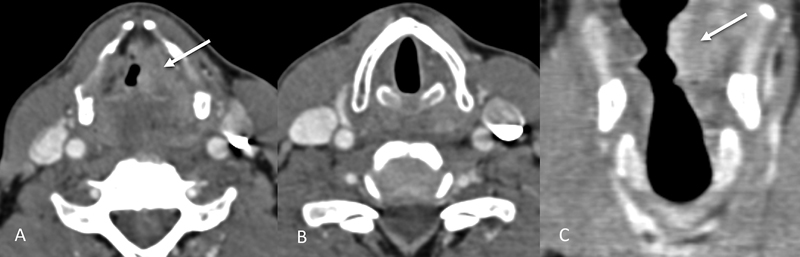

| Figure 4:Supraglottic laryngeal cancer. Axial and coronal CT images (A, C) showing a heterogeneously enhancing lesion (straight arrows) involving the left false vocal cord. The true vocal cords are normal in appearance and not involved as shown by the other axial image (B).